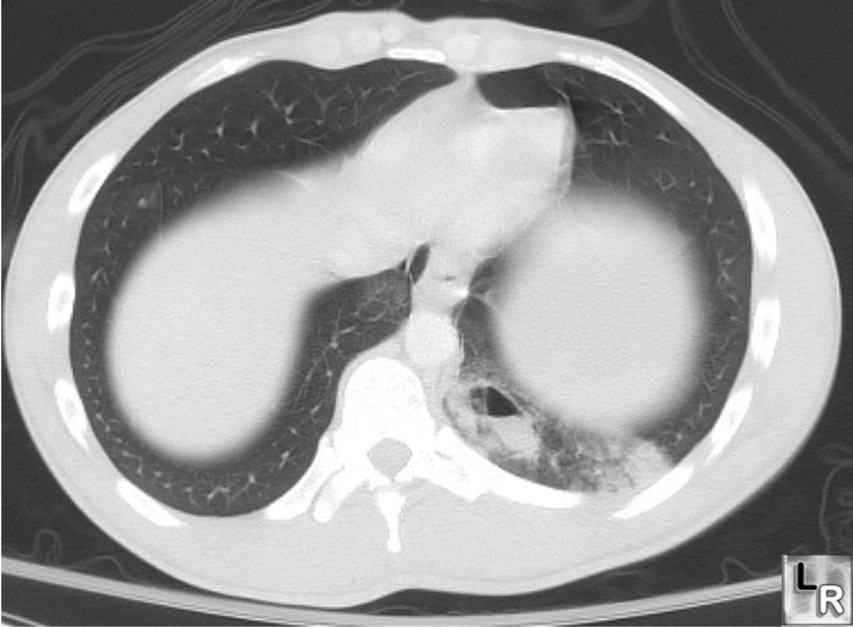

CT — Pulmonary Contusion (Annotated)

Axial CT showing pulmonary contusion with ground-glass opacification and consolidation following chest trauma

CT Downloaded 2026-03-15

Ct

Lung Window 120 kVp W:1500 L:-600

Wikimedia Commons: Pulmonary contusion CT arrow.jpg

CT — Pulmonary Contusion

CT showing bilateral pulmonary contusions with patchy areas of consolidation

Wikimedia Commons: Pulmonary contusion CT.jpg